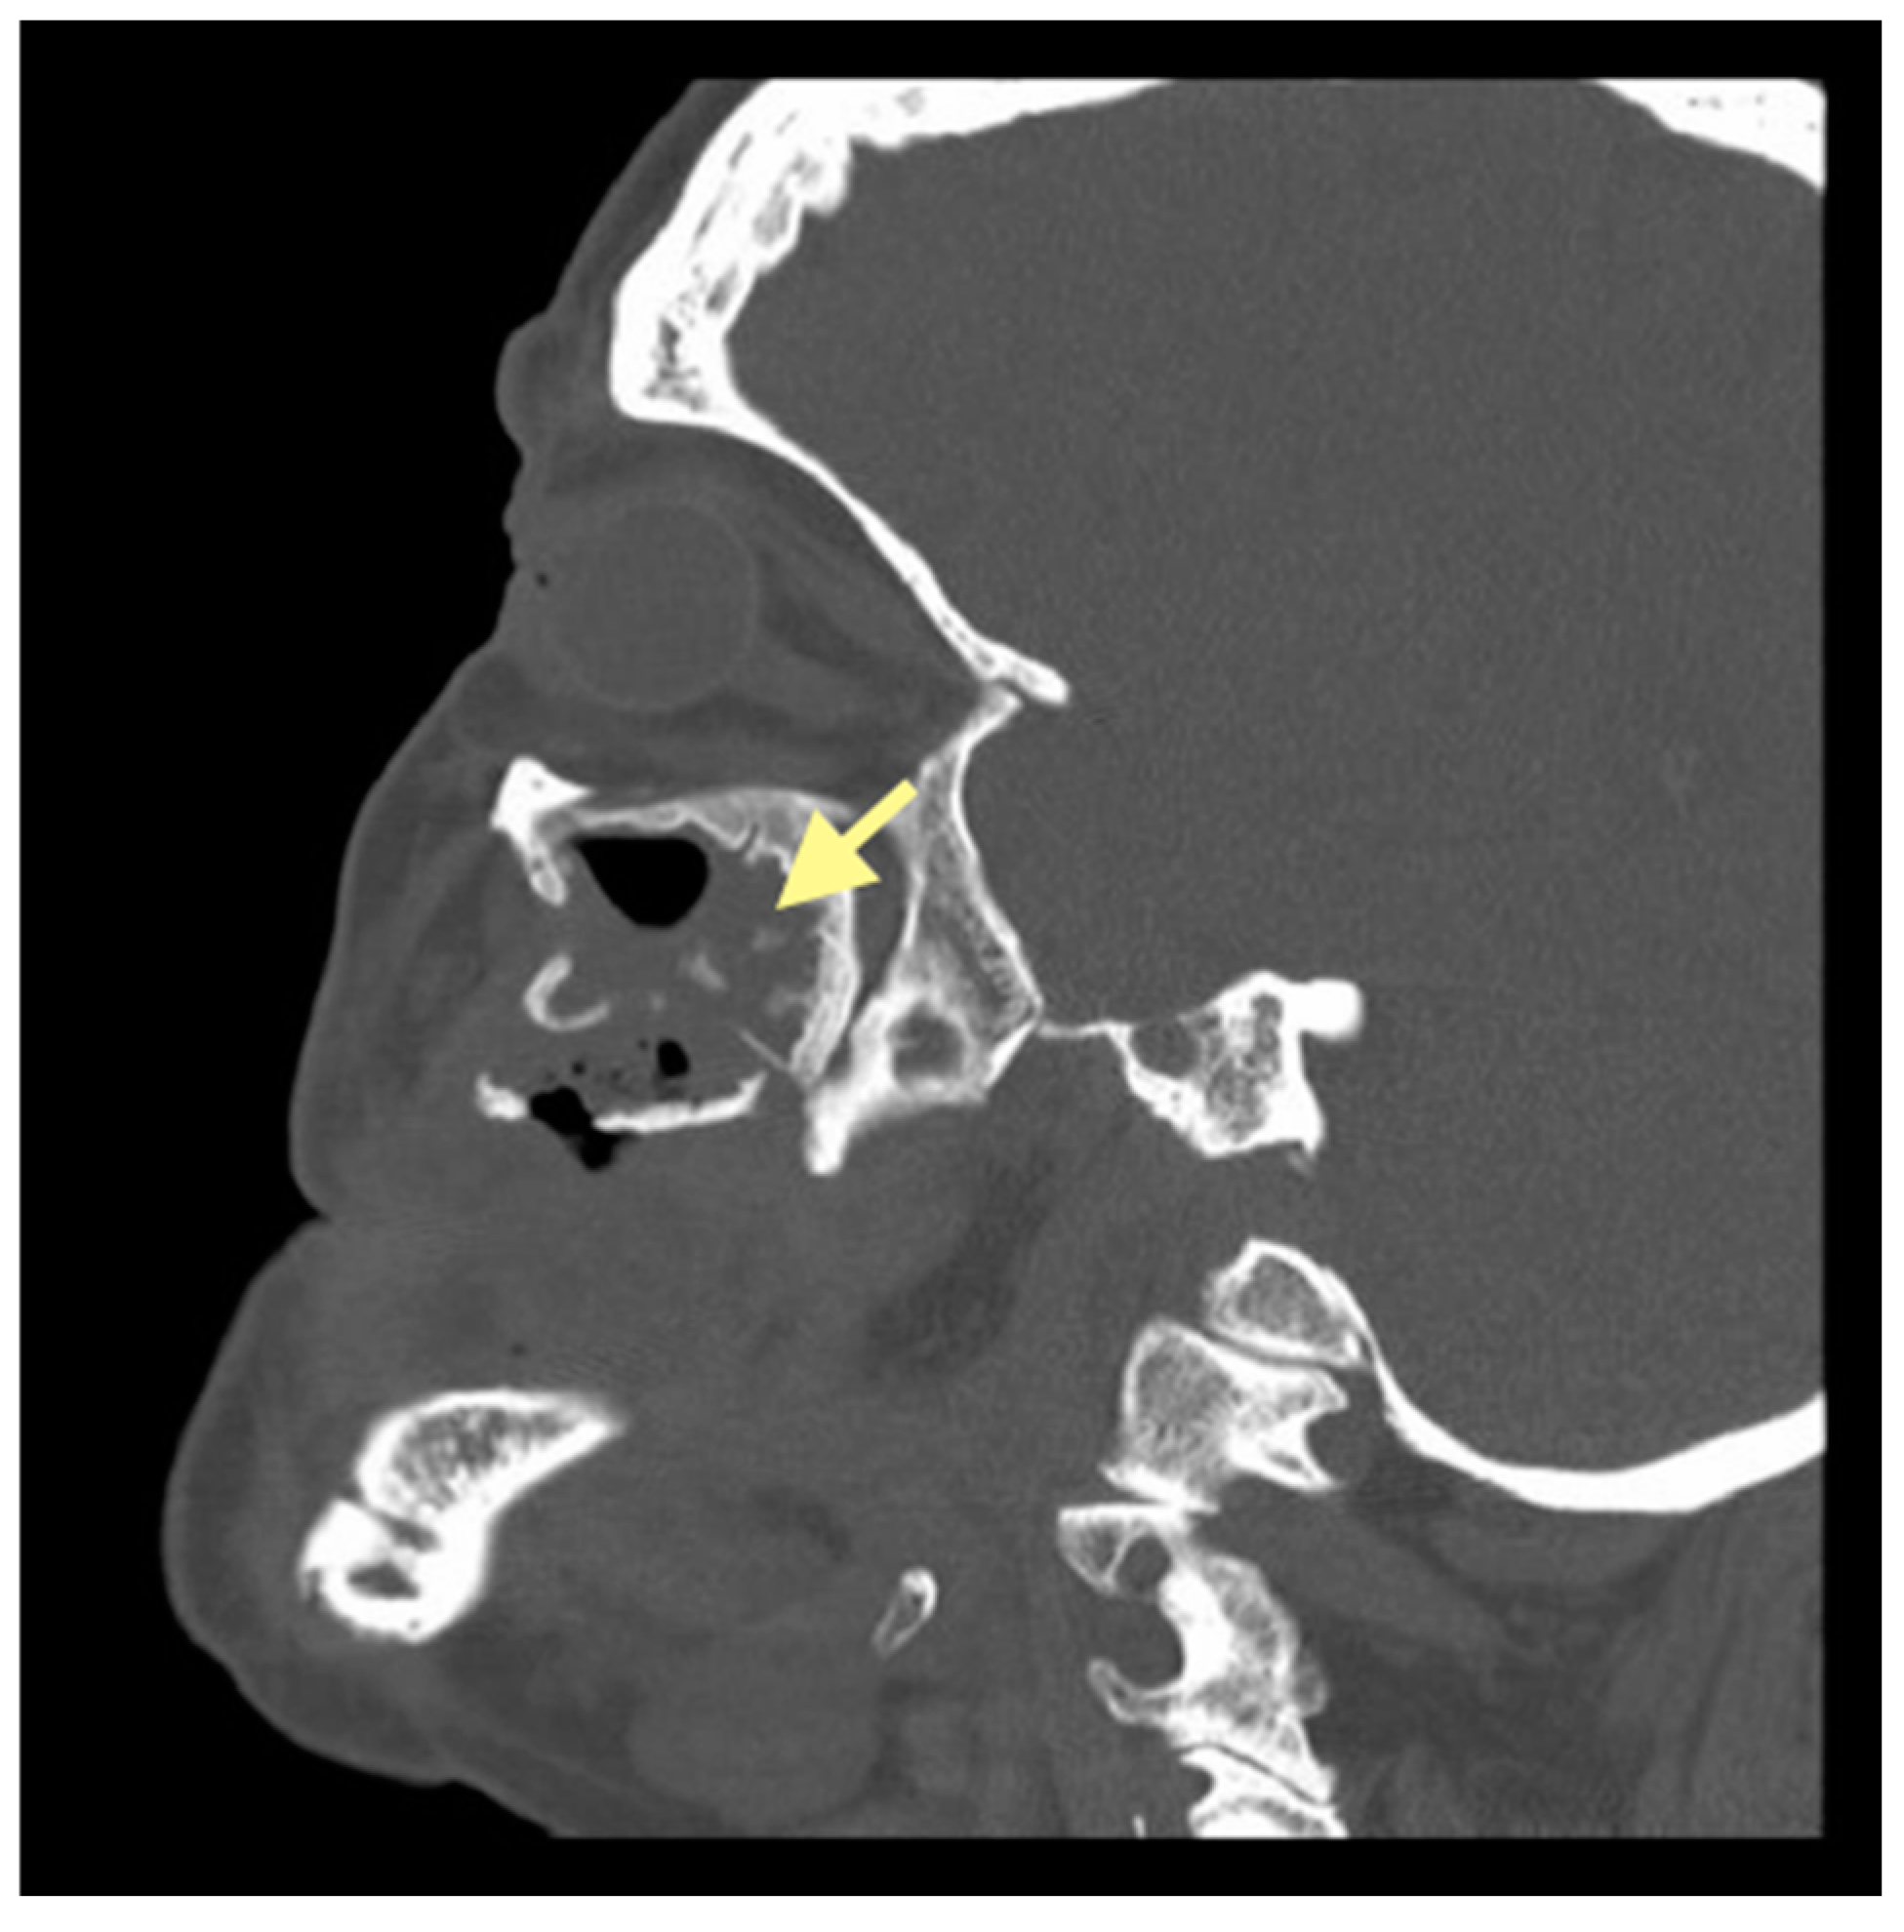

Figure 7.

CT of the head and facial bones (16 December 2024).